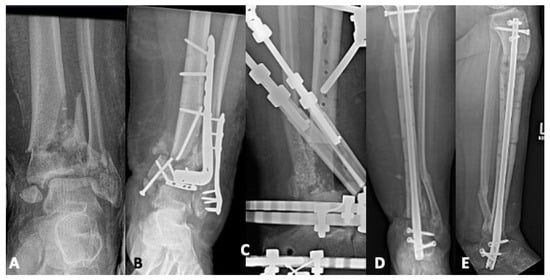

The Impact of Fibular Fixation Method on Pilon Fracture Healing

Background: Pilon fractures are associated with high-energy injuries, and there is presently much debate as to optimal fixation strategies and timing of intervention. There is little evidence comparing the type of fibular fixation during pilon fracture fixation. The purpose of this study was [...] Read more.

Background: Pilon fractures are associated with high-energy injuries, and there is presently much debate as to optimal fixation strategies and timing of intervention. There is little evidence comparing the type of fibular fixation during pilon fracture fixation. The purpose of this study was to compare fibular fixation methods in complex pilon injuries as it relates to pilon union rates and development of post-traumatic arthritis. Methods: This was a retrospective review from an urban Level 1 trauma center from January 2009 to May 2019, including patients age ≥ 18 who sustained a pilon fracture with an associated fibula fracture. Patients were allocated into one of three groups based on fibular fracture treated with plating, intramedullary device, or no fixation. Radiographic analysis was performed postoperatively and at final follow up to evaluate for tibial or fibular nonunion, malunion, talocrural angle, and ankle Kellgren–Lawrence grade. Results: Of the 107 patients in this study, 42 underwent surgical fixation of their fibular fracture. There were no differences with respect to tibial or fibular union rates amongst the three groups. Furthermore, there were no differences in the presence of radiographic ankle arthritis at final follow up. However, Kellgren–Lawrence arthritis grading did appear to be a more severe grade in patients who did not undergo fibular fixation (p = 0.001). Conclusions: Fibular intramedullary fixation does not appear to influence tibial or fibular nonunion rates as compared to plating in complex pilon injuries. Full article